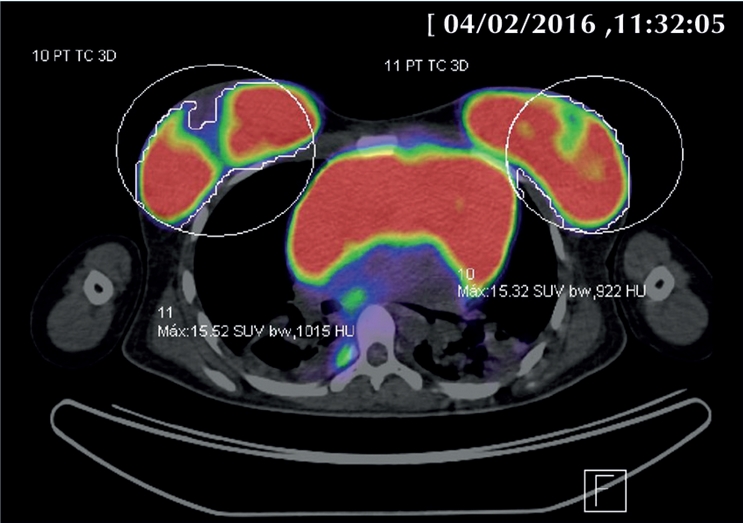

A la paciente se le realizaron estudios iniciales de la placa radiográfica de tórax (Figura 1) en la que se aprecia con masa mediastinal en mamas. Se inició abordaje radiológico con estudio de ultrasonografía pélvica y de mamas, así como tomografía computada mediastinal y abdómino pélvica donde se corrobora lesión tumoral en diversos niveles: mediastino, mamas y en pelvis a nivel parametrial, que el estudio de PET CT corroboró con un alto metabolismo de hasta 16 de SUVmax (Figura 2).